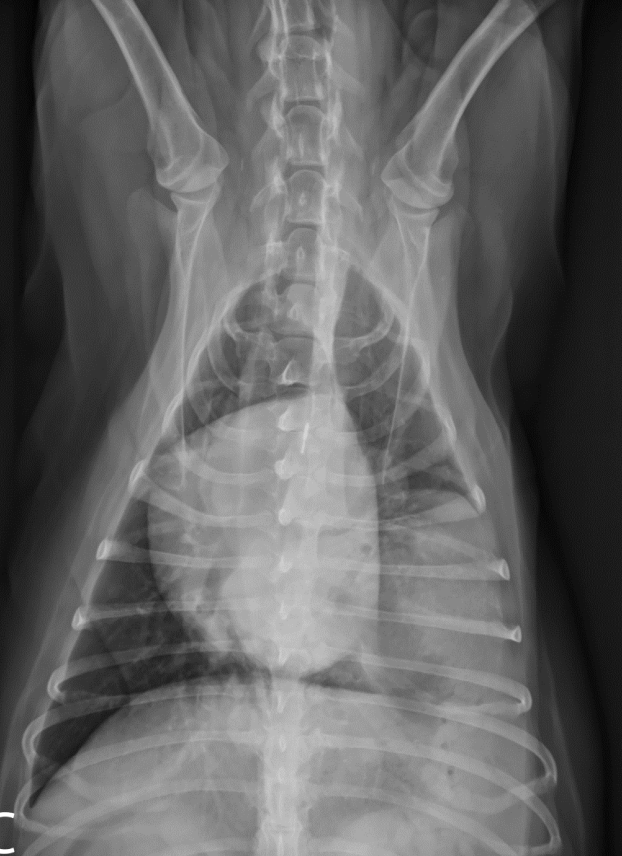

What is shown in this image?

gastroesophageal intussusception